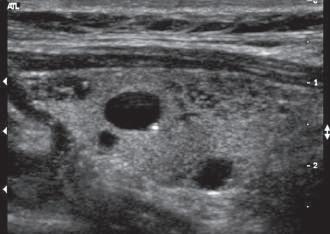

Refraction causes bending of the sound beam so that targets not along the axis of the transducer are insonated. Their reflections are then detected and displayed in the image. This may cause structures to appear in the image that actually lie outside the volume the investigator assumes is being examined (see Fig 1.7). Similarly, side lobes may produce confusing echoes that arise from sound beams that lie outside the main ultrasound beam (Fig. 1.28). These side lobe artifacts are of clinical importance because they may create the impression of structures or debris in fluid-filled structures (Fig. 1.29). Side lobes may also result in errors of measurement by reducing lateral resolution. As with most other artifacts, repositioning the transducer and its focal zone or using a different transducer will usually allow the differentiation of artifactual from true echoes.

FIG. 1.29 Side Lobe Artifact. Transverse image of the gallbladder reveals a bright internal echo (A) that suggests a band or septum within the gallbladder. This is a side lobe artifact related to the presence of a strong out-of-plane reflector (B) medial to the gallbladder. The low-level echoes in the dependent portion of the gallbladder (C) are also artifactual and are caused by the same phenomenon. Side lobe and slice thickness artifacts are of clinical importance because they may create the impression of debris in fluid-filled structures.

in what is actually a simple ovarian cyst.